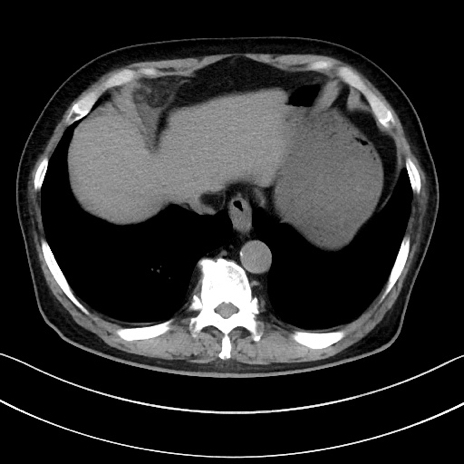

冠状断像